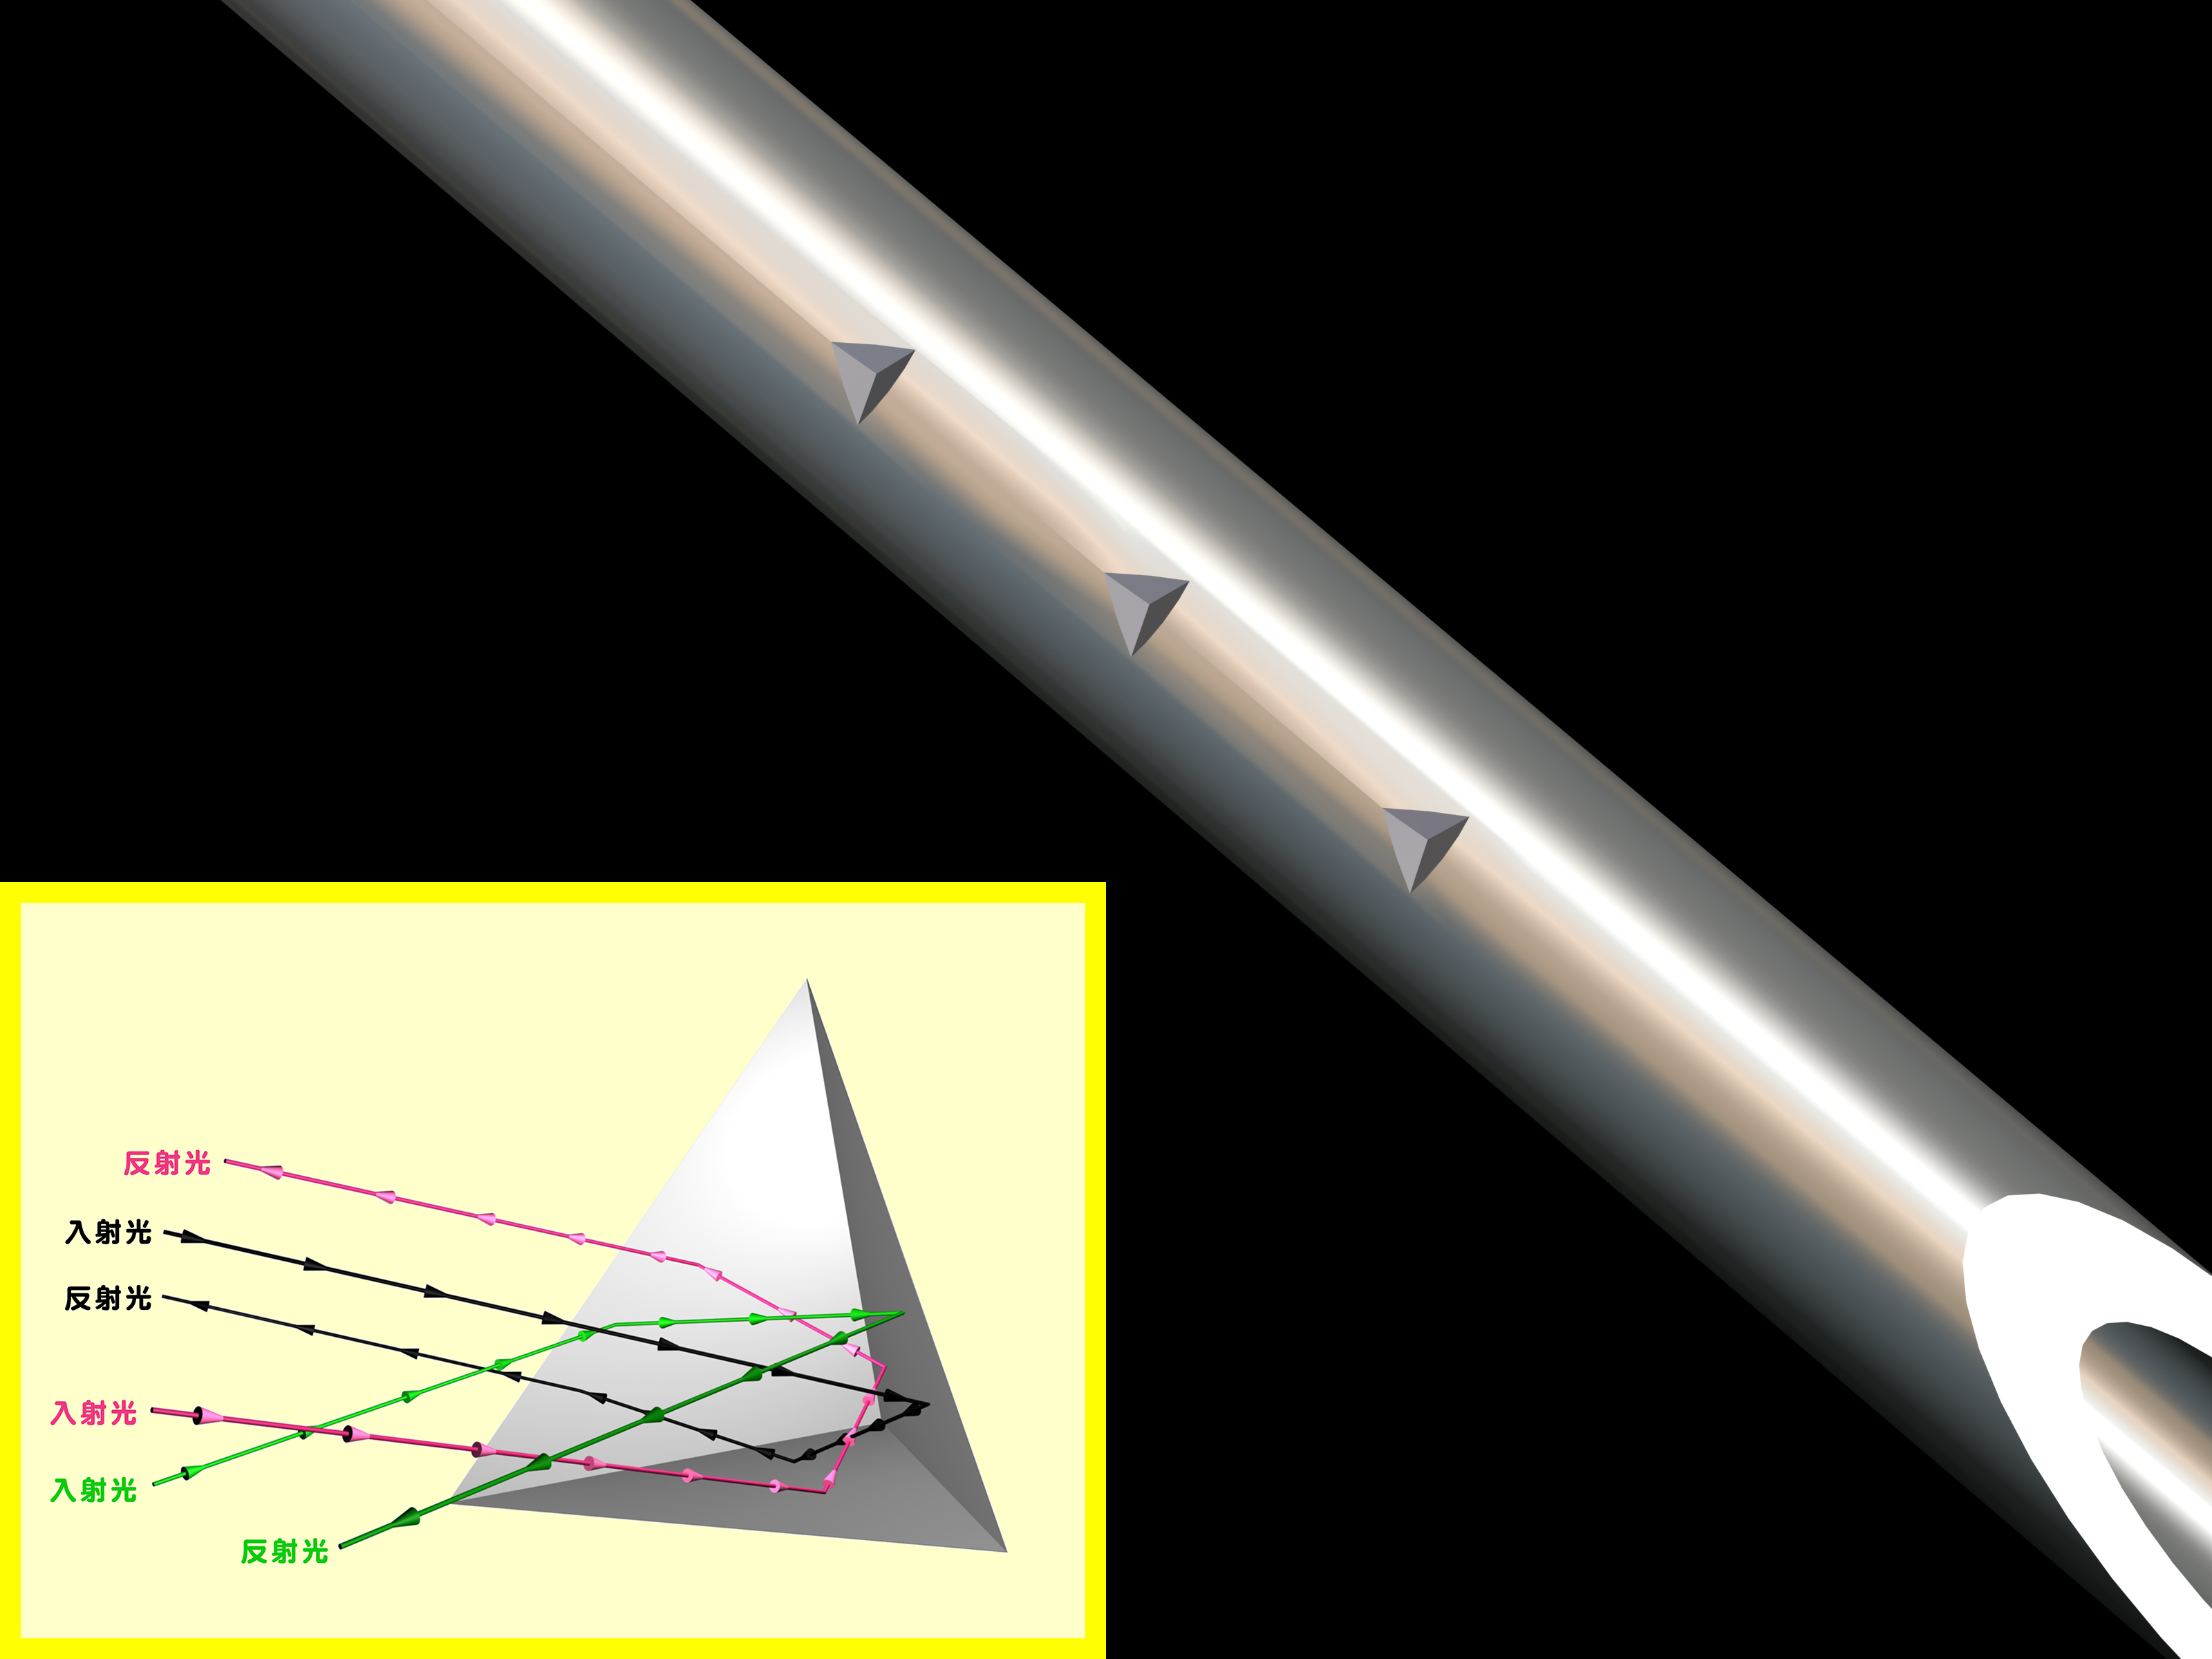

本発明は、超音波映像を観察しながら体内の目的部位へ針管を穿刺する超音波対応穿刺針に関するもので、穿刺針の所定位置に三角錐のコーナーキューブミラーを設けることで超音波下での針管の視認性を向上させたものである。

従来の超音波対応穿刺針は、体表に対して穿刺角度が大きくなる等の条件により、針管の超音波映像が極端に不明瞭になるという問題があった。これに対し、超音波の入射角と出射角が常に平行となる再帰反射に着目し、この性質をもつコーナーキューブミラーを針管の中心軸に平行に複数列、また、長手方向に複数列の配置で加工することにより、穿刺条件等によらず、針管の超音波映像を明瞭なものとした。